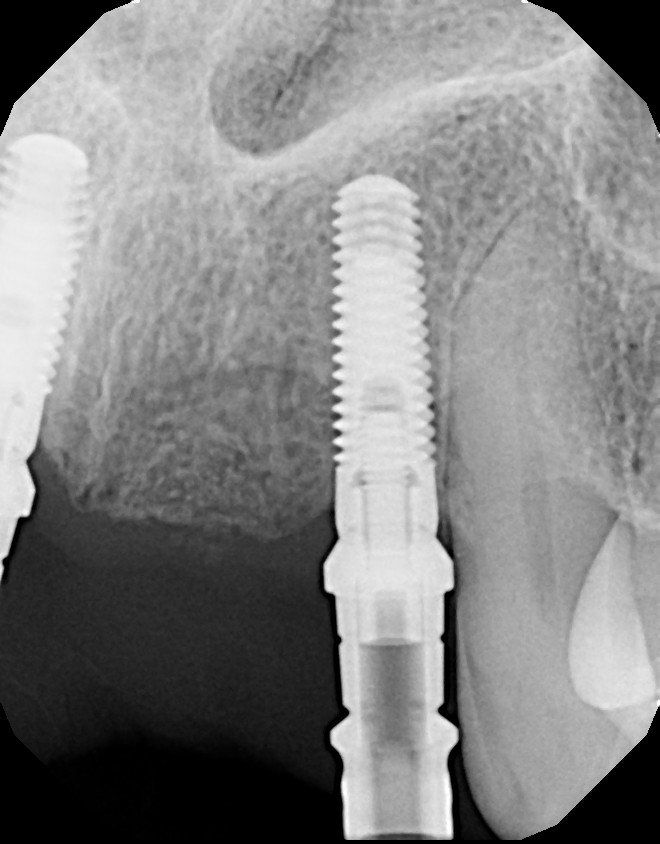

Over time, the jawbone associated with missing teeth atrophies or is reabsorbed, leaving a condition in which there is poor quality and quantity of bone sufficient for placement of dental implants. In situations like this, most patients are not candidates for dental implants.

However, today we have the ability to grow bone where needed, which gives us the opportunity to place implants of proper length and width and restore functionality and aesthetic appearance.

Bone grafting is used to repair implant sites with inadequate bone structure due to prior extractions, gum diseases, or injuries. We can obtain the bone from a tissue bank or from your own jaw, hip, or tibia (below the knee). Sinus bone grafts are also performed to replace bone in the posterior upper jaw. Additionally, special membranes can be utilized that dissolve under the gum and protect the bone graft and encourage bone regeneration; a process called guided bone regeneration or guided tissue regeneration.

A sinus graft or sinus lift graft is the solution. The surgeon enters from a sinus where the upper teeth used to be, and the sinus membrane is lifted up for bone to be inserted into the floor of the sinus. The floor of the sinus is the roof of the upper jaw. After months of healing, the bone becomes part of the jaw and dental implants can then be inserted in the new sinus bone.